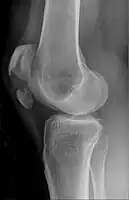

A vertical patella fracture with the fracture line marked by a black arrow

Diagnosis is based on symptoms and confirmed with X-rays.[3] In children an MRI may be required.[3]